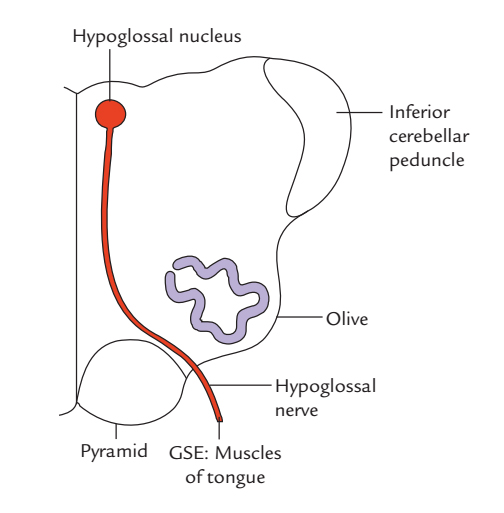

Motor Cranial Nerves – Anatomy, Functions & Components | Kenhub

Hypoglossal nerve-Functional component-Nucleus-Course-Distribution …

Motor cranial nerves: Anatomy, functions and components | Kenhub

Hypoglossal Nerve Intermedullary Course

Hypoglossal Nerve Intermedullary Course